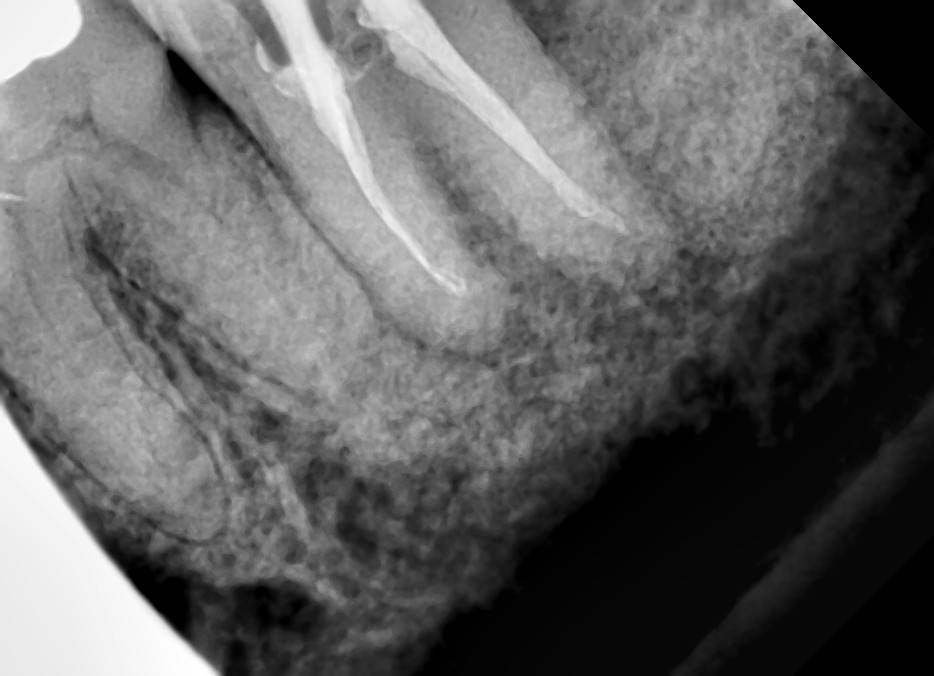

Then pandemic struck, where I probably have only made two visits/adjustments during the whole year of 2020. But even before the start of the lockdown (or after about 17 months of treatment), my teeth and jaw have miraculously aligned in spite of my age. Before starting with the treatment plan, the TMJ specialist told me that there is no guarantee of success (or the desired results may not be achieved) given my age, that they even made me sign a waiver. Though I now understand my body (where I wrote about understanding and listening to your body in my article https://columbusbee.blog/2020/03/28/my-gut-feel-against-the-virus/), I’m still surprised at times on how my body works. Like when I underwent root canal treatment also with the same clinic this year. I have a molar tooth (the tooth at the farthest end) that was decaying and that the infection has already spread both in the gums and the jawline where the x-ray shows loss of bone mass and gum tissue due to infection. Two dentists of the clinic (from different branches) have suggested tooth extraction but after learning what I’ll go thru if I decide to have tooth implant to replace the extracted tooth (denture is no longer an option coz being the farthest tooth, there is only one adjacent tooth to support the same), I decided (and insisted) to save the infected tooth instead thru root canal treatment. Again, miraculously, what seems to be a hopeless case has proven naysayers wrong by just having faith on the body’s healing powers (coupled with mental affirmation that the tooth will be saved). After several bi-weekly visits in a span of 3 months (with the same number of COVID swab test for every visit), the tooth was saved where the infection on the gum tissue started to disappear, the bone mass on the jawline started to regenerate, and what used to be wobbly is now a tooth firmly rooted. My body works in mysterious ways.

(Left) Around the tip of the root of the tooth is a hollow dark spot which is a manifestation of gum tissue infection and loss of bone mass on the jawline. (Right) Three months after the start of the root canal treatment, you see a significant improvement where the dark spot is no longer there which means that the infection is gone and gum tissue and bone mass start to regenerate.